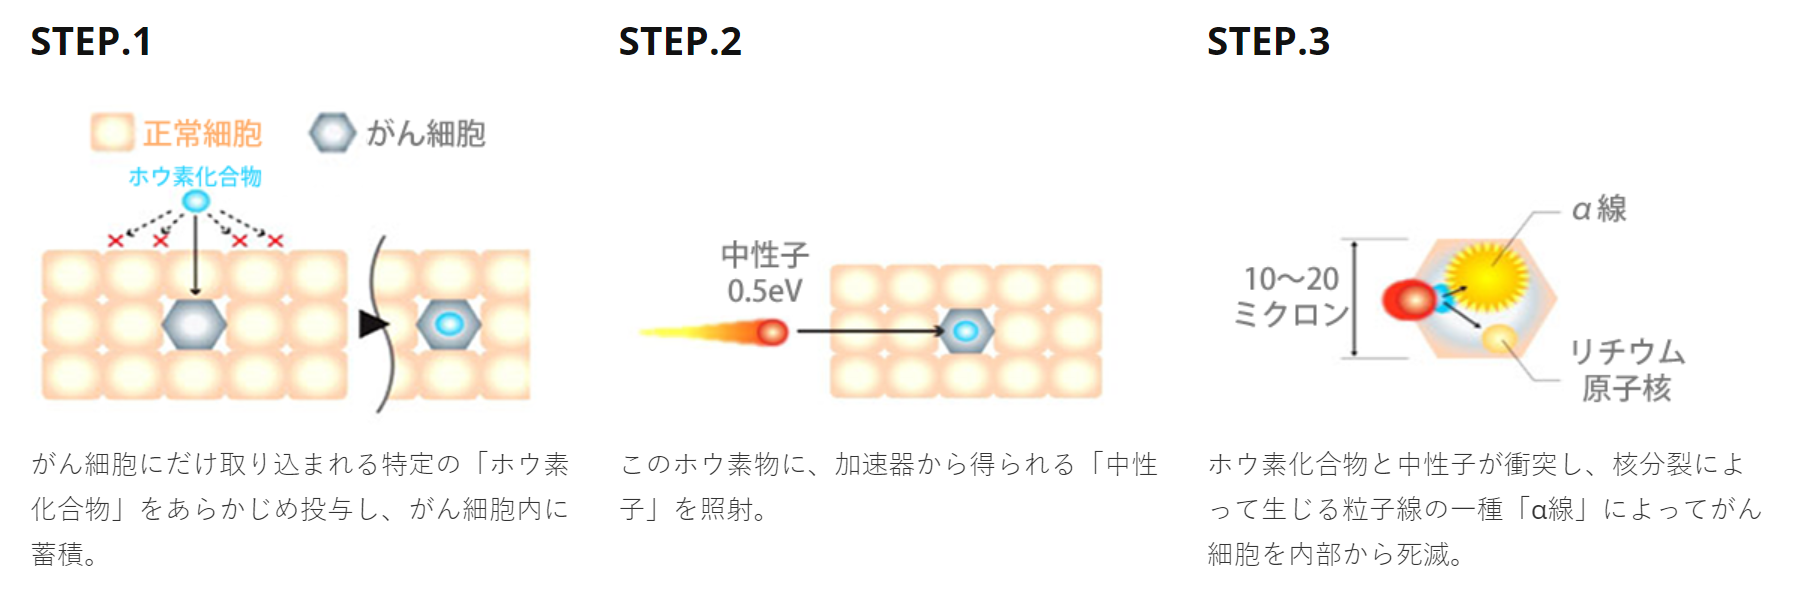

- 精 5年无病生存率达63%!放疗新技术-质子治疗优势尽显

- 精 3年总生存率100%!终结癌细胞的质子治疗,放射治疗中的利刃

- 精 局部控制率达69.8%!质子治疗在众多肿瘤中游走,头颈癌、前列腺癌、肝癌等患者受益良多

- 精 又是一把抗癌武器-质子治疗